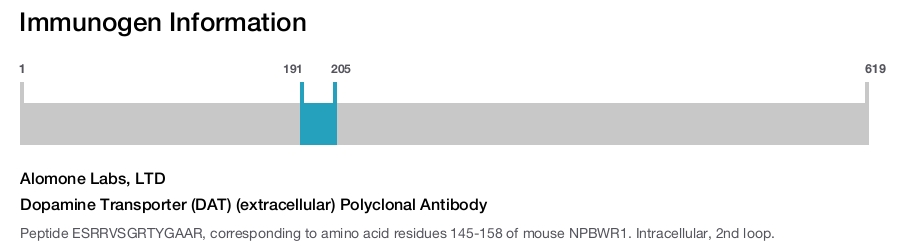

Dopamine Transporter (DAT) (extracellular) Polyclonal Antibody

Immunogen sequence: ESRRVSGRTYGAAR

The Dopamine Transporter (DAT) is responsible for the reaccumulation of dopamine after it has been released. DAT antibodies and antibodies for other markers of catecholamine biosynthesis are widely used as markers for dopaminergic and noradrenergic neurons in a variety of applications including depression, schizophrenia, Parkinson's disease and drug abuse.